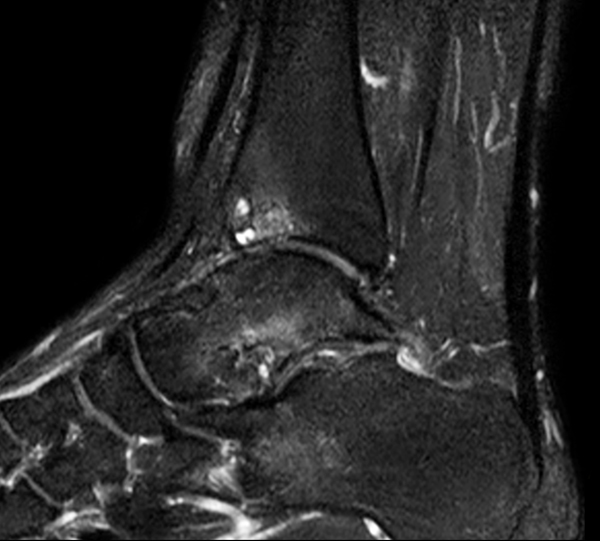

Sagittal PDW SPAIR